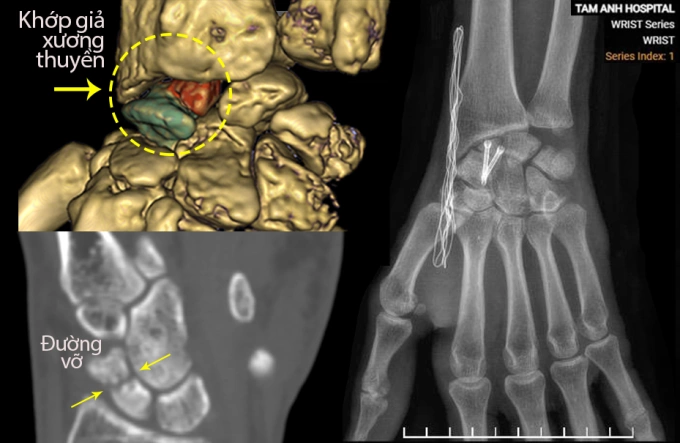

Tổn thương khớp giả của anh Tuấn (trái) được phẫu thuật cố định (phải). Ảnh: Bệnh viện Đa khoa Tâm Anh

Anh Tuấn được phẫu thuật cố định ổ khớp giả xương thuyền sử dụng xương ghép tự thân. Bác sĩ rạch đường mổ 3 cm trên vùng cổ tay, dùng khoan mài sạch hai diện gãy của ổ khớp giả, loại bỏ các đầu "xương hóa đá". Sau đó, êkíp mở đường mổ ở hông bệnh nhân lấy một mảnh xương xốp giữa mào chậu ghép lên khoảng hở giữa hai đầu gãy xương thuyền vừa xử lý. Các đoạn xương được cố định bằng hai vít chuyên dụng.

Quá trình phẫu thuật được thực hiện dưới máy chụp X-quang liên tục (C-arm), giúp xác định chính xác vị trí khớp giả, trục đặt vít Herbert theo kế hoạch mổ 3D, tránh lệch chỉ vài độ có thể khiến vít xuyên khỏi xương thuyền vốn rất nhỏ.